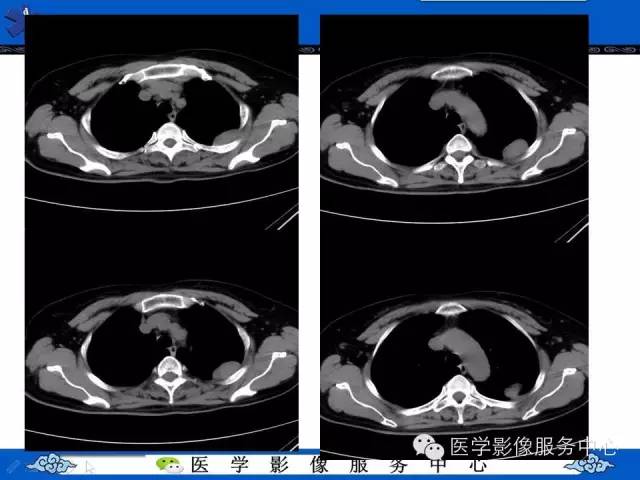

胸膜孤立性纤维瘤1例CT影像表现与鉴别

【病例】胸膜孤立性纤维瘤1例CT影像表现与鉴别